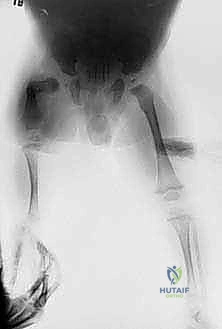

معرض الصور السريرية لمراحل التثبيت والتطويل:

معرض إضافي لصور الأشعة والمتابعة الدقيقة للحالات: